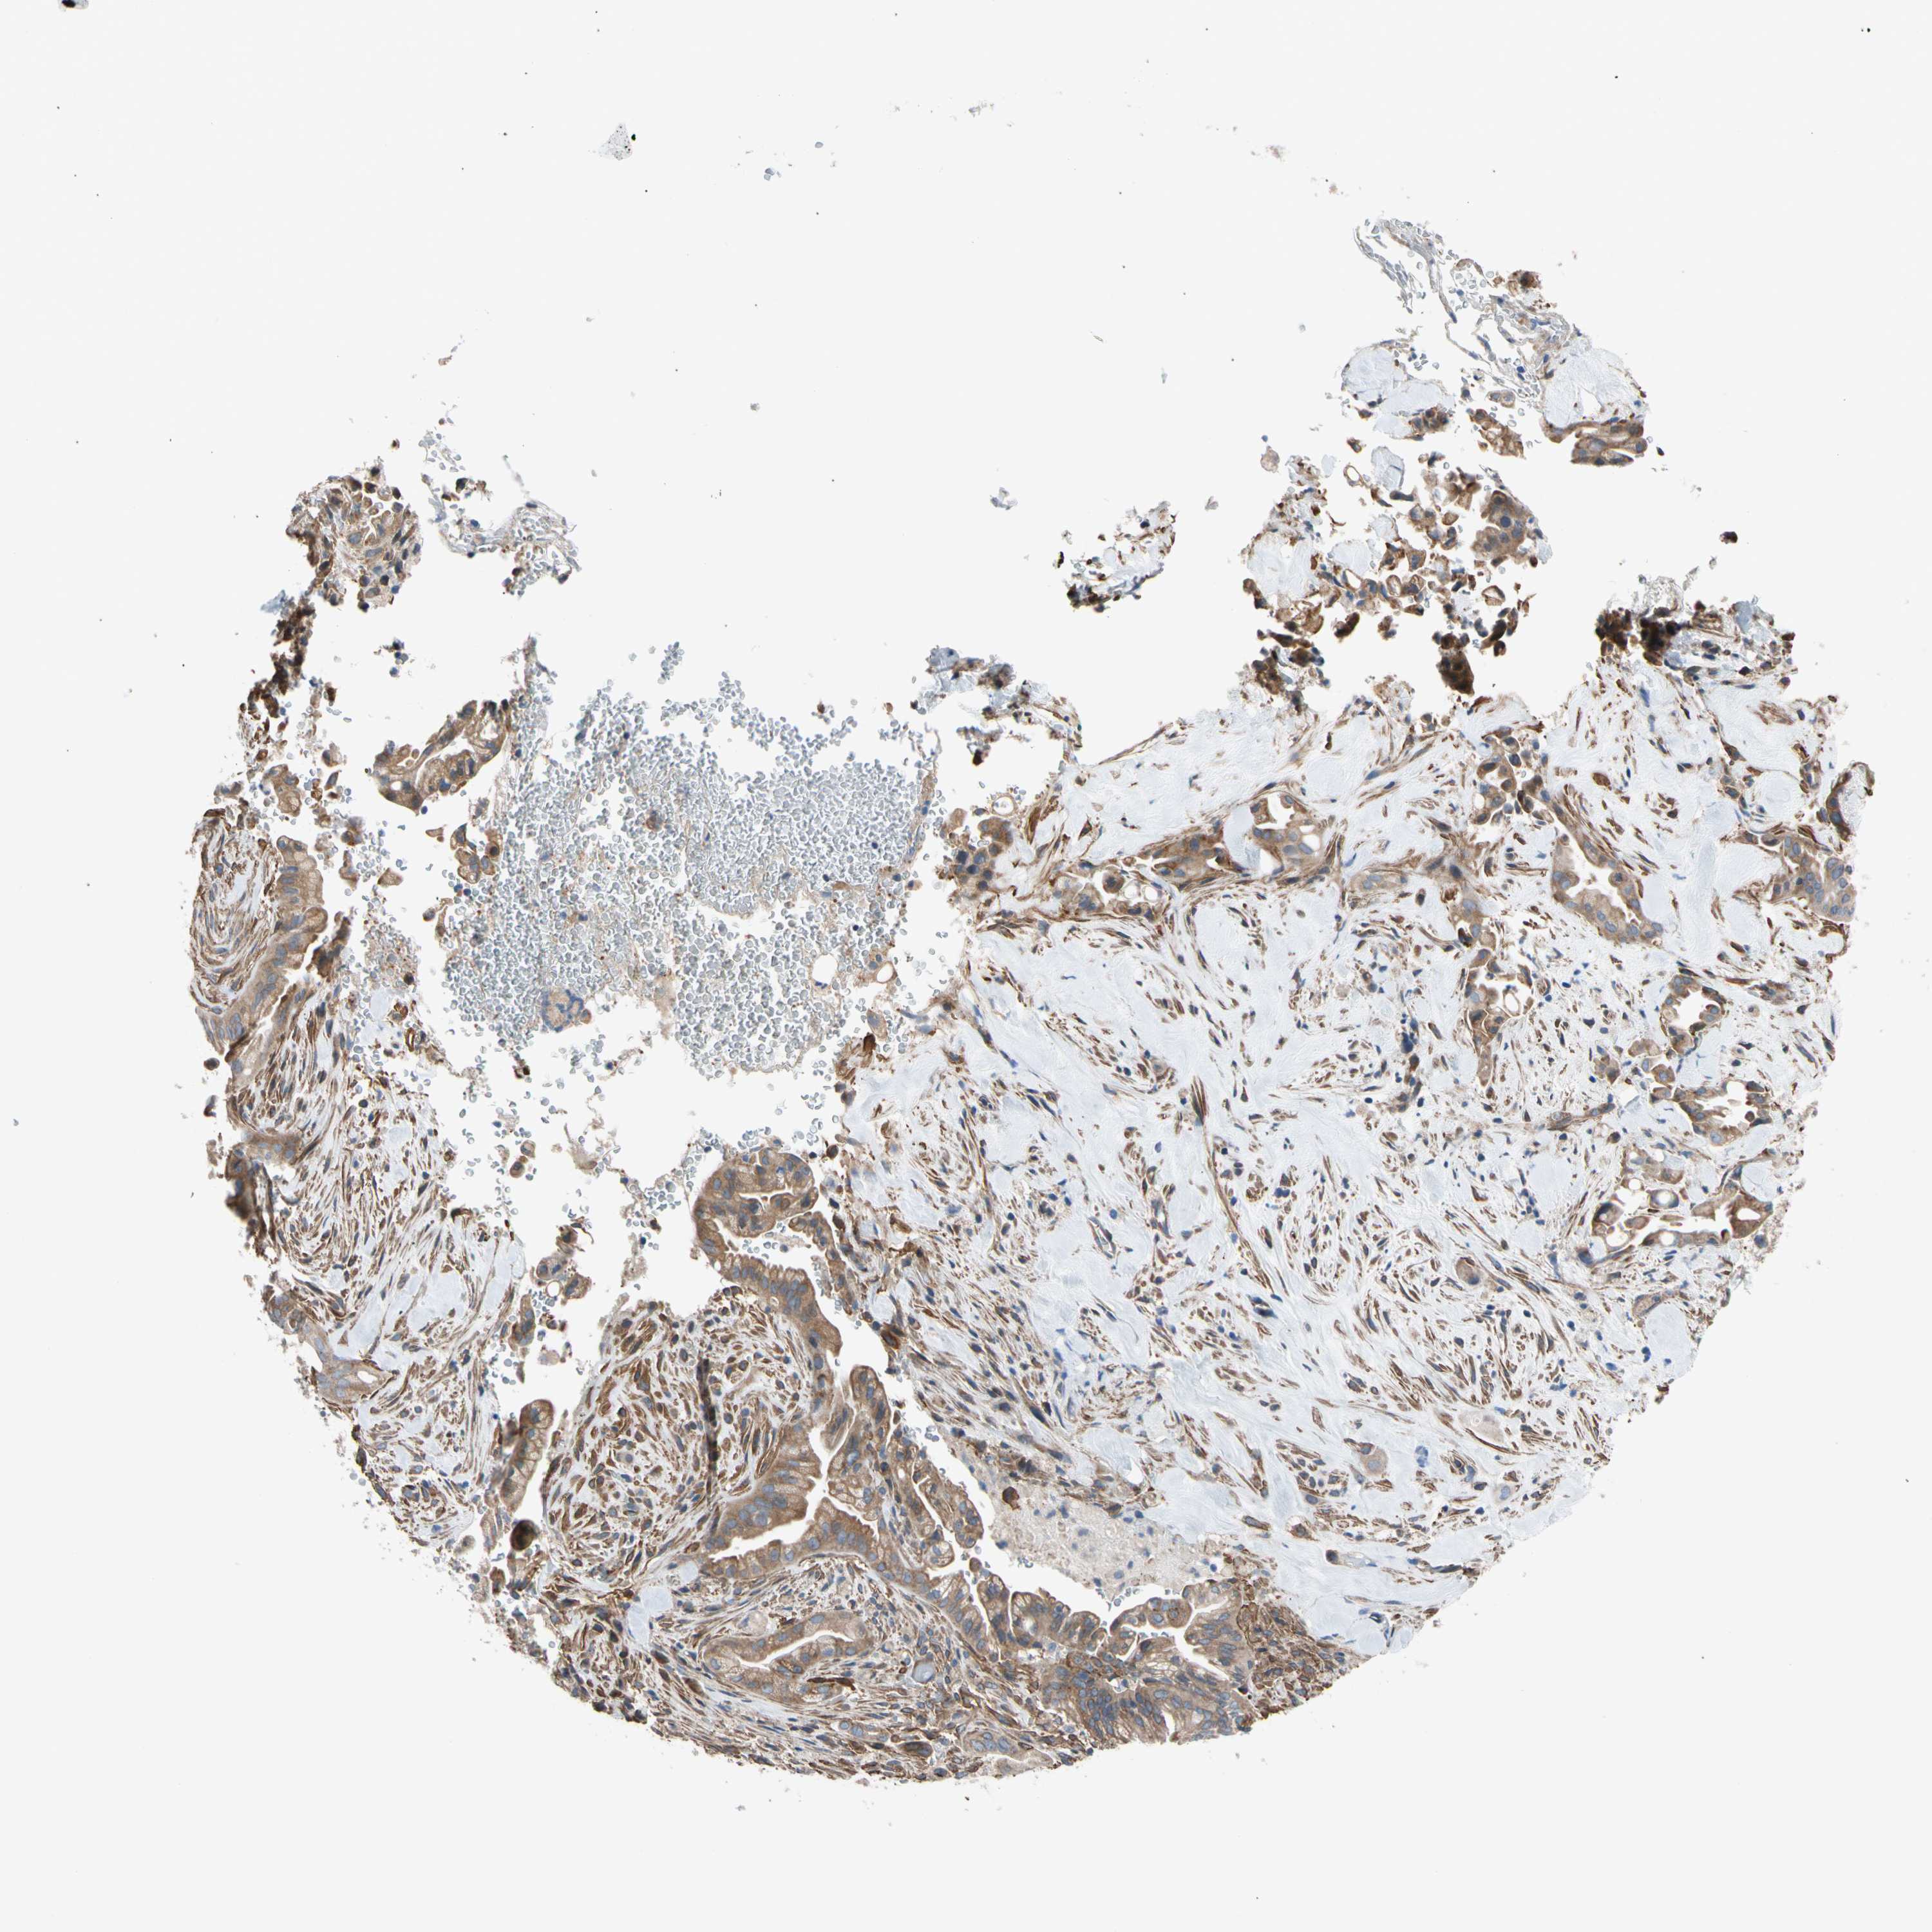

LIVER CANCER - Protein expressioni

A mouse-over function shows sample information and annotation data. Click on an image to view it in a full screen mode. Samples can be filtered based on level of antibody staining by selecting one or several of the following categories: high, medium, low and not detected. The assay and annotation is described here.

Note that samples used for immunohistochemistry by the Human Protein Atlas do not correspond to samples in the TCGA dataset.

Antibody stainingi

Antibody staining in the annotated cell types in the current human tissue is reported as not detected, low, medium, or high, based on conventional immunohistochemistry profiling in selected tissues. This score is based on the combination of the staining intensity and fraction of stained cells.

Each image is clickable and will lead to virtual microscopy that enables deeper exploration of all samples and also displays staining intensity scores, fraction scores and subcellular localization as well as patient and tissue information for each sample.

Antibody HPA008183

Antibody HPA053882

Antibody CAB019313

Staining

High

Medium

Low

Not detected

Intensity

Strong

Moderate

Weak

Negative

Quantity

>75%

75%-25%

<25%

None

Location

Nuclear

Cytoplasmic/membranous

Cytoplasmic/membranous,nuclear

Cholangiocarcinoma

Carcinoma, Hepatocellular, NOS